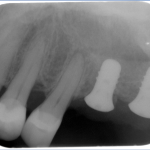

The sinus graft makes it possible for many patients to have dental implants in the upper back teeth area when years ago there was no other option besides wearing loose dentures. The maxillary sinuses are behind your cheeks and on top of the upper teeth. These sinuses are empty, air-filled spaces. Some of the roots of the natural upper teeth extend up into the maxillary sinuses. When these upper teeth are removed, there is often just a thin wall of bone separating the maxillary sinus and the mouth. Dental implants need bone to hold them in place. When the sinus wall is very thin, it is impossible to place dental implants in this bone.

The key to a successful and long-lasting dental implant is the quality and quantity of jaw bone to which the implant will be attached. If bone loss has occurred due to injury or periodontal disease, a sinus augmentation can raise the sinus floor and allow for new bone formation.

In the most common sinus augmentation procedure, a small incision is made on the premolar or molar region to expose the jaw bone. A small opening is cut into the bone, and the membrane lining the sinus is pushed upward. The underlying space is filled with bone grafting material, either from your own body or from a cadaver. Sometimes, synthetic materials that can imitate bone formation are used. After the bone is implanted, the incision is stitched up and the healing process begins.

After several months of healing, the bone becomes part of the patient’s jaw and dental implants can be inserted and stabilized in this new sinus bone.

If enough bone between the upper jaw ridge and the bottom of the sinus is available to stabilize the implant well, sinus augmentations and implant placement can sometimes be performed as a single procedure. If not enough bone is available, the sinus augmentation will have to be performed first, then the graft will have to mature for several months, depending upon the type of graft material used. Once the graft has matured, the implants can be placed.